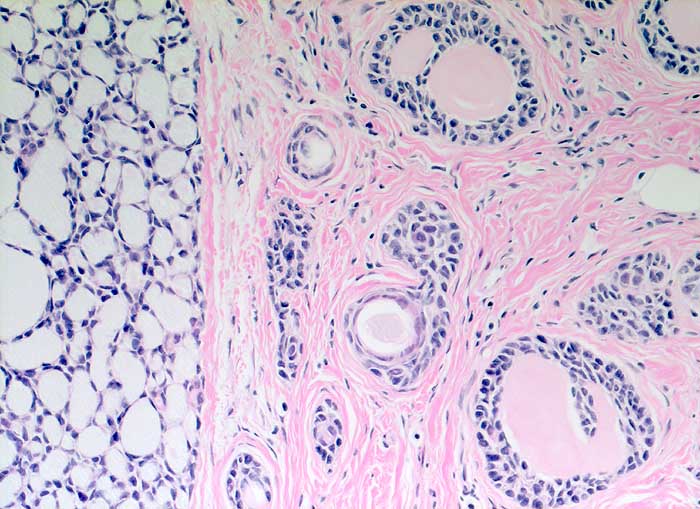

Adenoidzystisches Karzinom der Mamma

Adenoidzystische Karzinome machen lediglich 1% aller Mammakarzinome aus. Die Morphologie ist identisch mit dem gleichnamigen Tumor der Speicheldrüsen. Die Zellen des adenoidzystischen Karzinoms bilden kohäsive Verbände und Drüsen oder mikrozystische Strukturen. Die Tumorzellen sind klein und monomorph, die Kern-Zytoplasmarelation ist hoch. Die Kerne sind dunkel, rund bis oval oder angulär und enthalten bisweilen einen kleinen Nukleolus. Azelluläre hyaline Körperchen aus mucoidem Material, welche die Hohlräume der intakt aspirierten kribriformen Strukturen ausfüllen, sind besonders typisch. Das mucoide Material kann auch verzweigte oder fingerartige abgerundete Strukturen ausbilden.